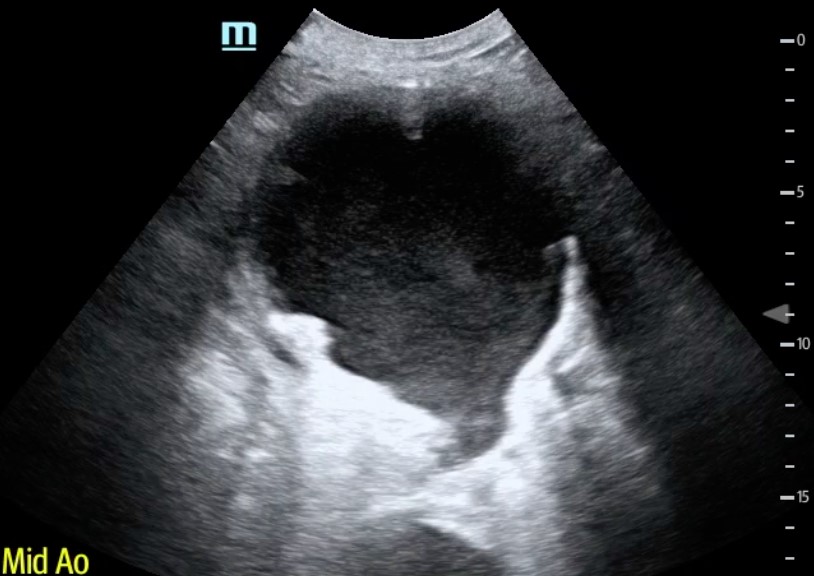

Point-of-care ultrasound (POCUS) performed at the patient’s bedside demonstrated a large, 11 cm, abdominal aortic aneurysm (AAA) with visible echogenic turbulent blood flow (Figure 1, Video 1). With the assistance of Color Doppler, we were able to confirm that the AAA had ruptured with active hemorrhage (Figure 2, Video 2). Volume resuscitation with IV fluids and blood products was initiated, while Vascular Surgery consult was called and arrived at the bedside within 15 minutes. The patient was taken emergently to the OR for successful endovascular aortic repair.

Figure 1. AAA B-mode with turbulent blood flow.